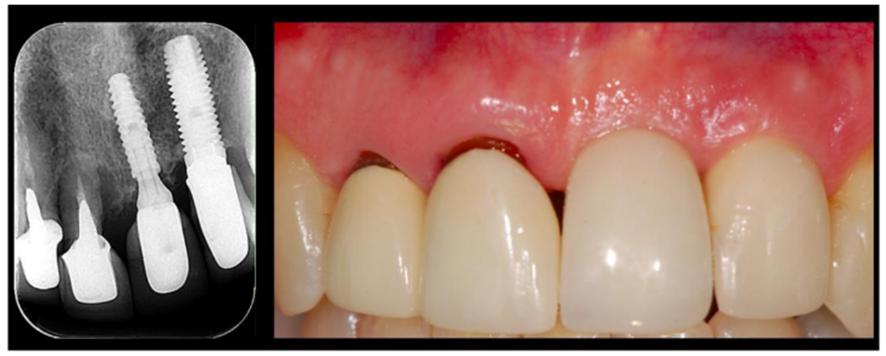

Outro aspecto interessante a ser avaliado é o comportamento dos tecidos moles peri-implantares, especialmente do implante 22. Este implante foi realizado antes de o paciente aparecer para nós, aproximadamente há uns 20 anos. Mesmo com todas as dimensões avantajadas deste implante, além da sua plataforma hexagonal interna, o implante estava em excelentes condições ósseas e com estabilidade marginal dos tecidos duros e moles. Muito provavelmente este resultado se deu pela colocação de um pilar protético tipo switching, a fim de se ganhar mais espaço para os tecidos moles.

O fenômeno observado nos implantes com plataforma switching segue os mesmos princípios dos pilares Ideale fabricados pela Implacil Osstem. Esta configuração de pilares mais estreitos e com cintas metálicas superiores a 1,5mm, conferem uma estabilidade marginal dos tecidos moles peri-implantares bastante segura, pois respeita o espaço biológico para acomodação do epitélio juncional e da adaptação conjuntiva.